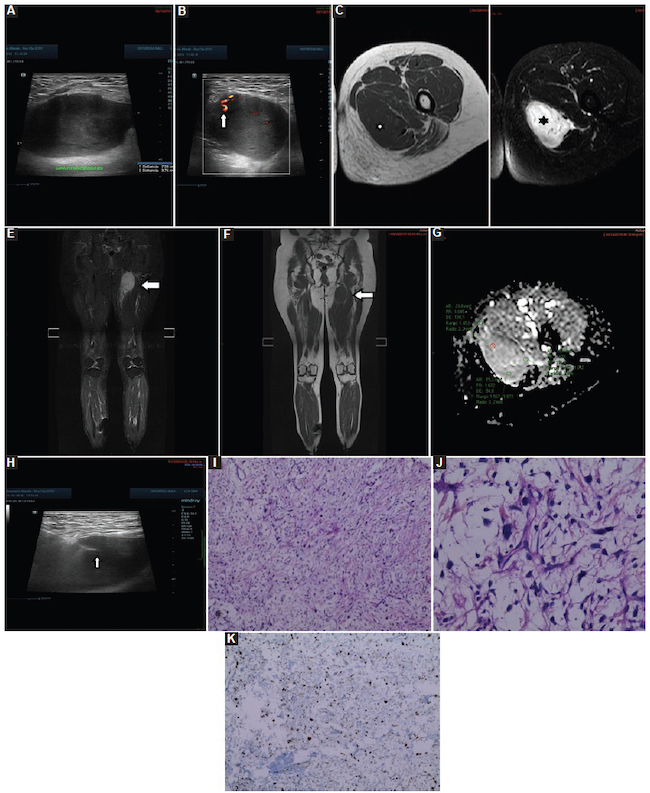

Infección: fueron 12 casos, con un valor medio de CDA de 0,68 ± 0,17 × 10−3 mm2/s (0,40-0,90) (Fig. 8), de los cuales hubo cinco en los miembros superiores, tres en la pelvis, tres en los miembros inferiores y uno en el cuello.

Encondromas: fueron 11 casos, con un valor medio de CDA de 1,65 ± 0,31 × 10−3 mm2/s (1,30-2,10) (Fig. 9), de los cuales fueron cuatro en el fémur, cuatro en el húmero, uno en la tibia, uno en el peroné y uno en la falange.

Lipomas: fueron nueve casos, con un valor medio de CDA de 1,66 ± 0,31 × 10−3 mm2/s (1,30-2,10) (Fig. 10), de los cuales fueron cuatro en los miembros superiores, cuatro en los miembros inferiores y uno adyacente a la parrilla costal.

Quiste óseo simple: fueron nueve casos, con un valor medio de CDA de 2,02 ± 0,54 × 10−3 mm2/s (1,30-2,70) (Fig. 11), de los cuales fueron dos en los miembros superiores, seis en los miembros inferiores y uno en la pelvis.

Quiste de inclusión epidérmico: fueron siete casos, con valor medio de CDA de 1,09 ± 0,33 × 10−3 mm2/s (0,68-1,5) (Fig. 12).